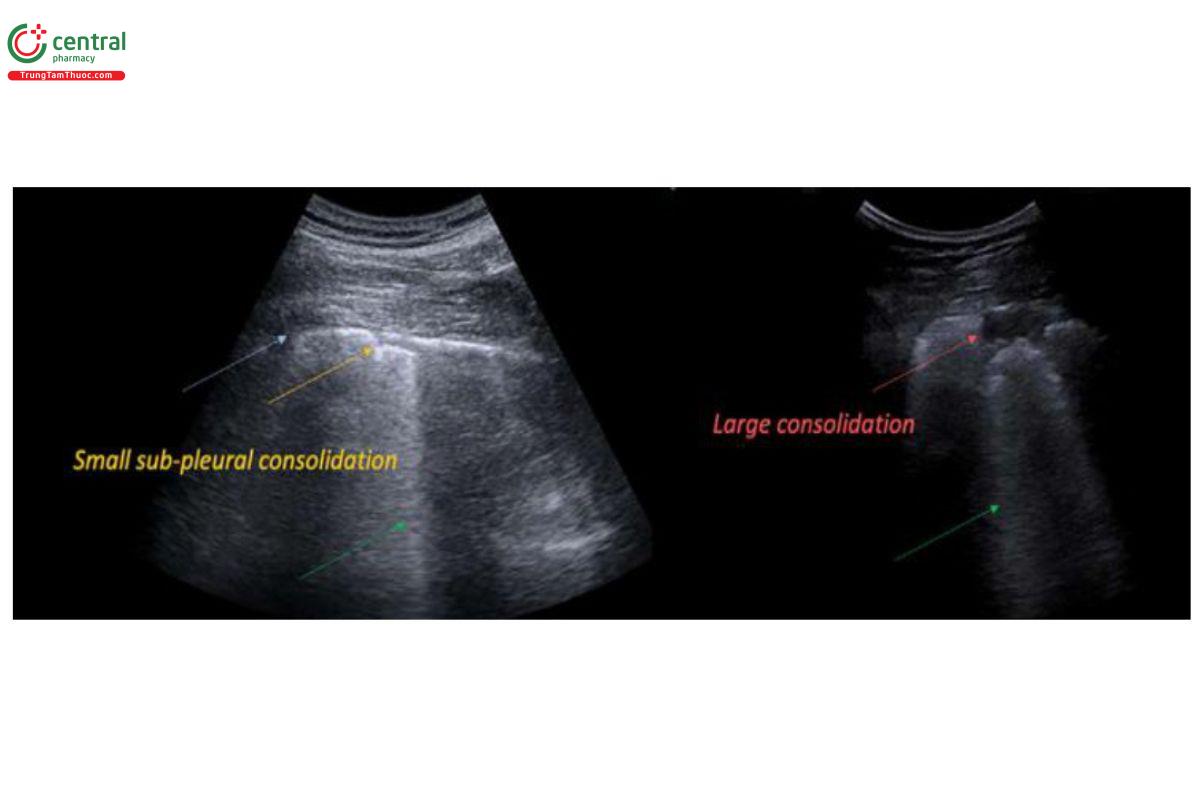

Dấu hiệu đông đặc phổi: Là vùng giảm âm chủ yếu dưới màng phổi hoặc vùng giảm âm có mật độ giống gan. Hình ảnh đông đặc trong viêm phổi thường có ranh giới không đều, không tròn. Khi có sự đông đặc dưới màng phổi, đường màng phổi không rõ ràng và sự trượt màng phổi giảm hoặc không có. Đông đặc có thể kèm dấu hiệu phế quản hơi (biểu hiện bằng các điểm tăng âm và/hoặc hình ảnh đường), giúp phân biệt với xẹp phổi [25, 32].

Đánh giá mức độ và độ rộng của viêm phổi trên siêu âm được mô tả bằng điểm LUS [29, 30, 31].

- Bảng 1. Tiêu chuẩn điểm LUS đánh giá mức độ viêm phổi trên siêu âm

| Điểm | Dấu hiệu hình ảnh siêu âm |

| 0 | Dấu hiệu đường A và dấu hiệu trượt phổi rõ ràng hoặc có 1-2 dấu hiệu đường B |

| 1 | ≥3 đường B hoặc đông đặc nhỏ dưới màng phổi được ngăn cách bởi các đường màng phổi nhẵn đều |

| 2 | Nhiều đường B kết hợp hoặc các đông đặc nhỏ dưới màng phổi được ngăn cách bởi các đường màng phổi không đều |

| 3 | Đông đặc dưới màng phổi lớn hơn 1 x 2cm |